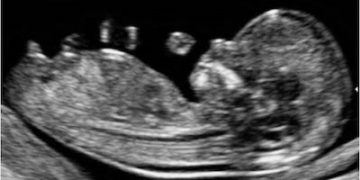

How To Do Luglio 2023: terminologia e classificazione MUSA

Cari soci, questo mese un nuovo video "How to do", dedicato alla terminologia e classificazione MUSA Grazie a Francesca Arezzo! Il video è accessibile ai soli soci SIEOG attraverso questo...